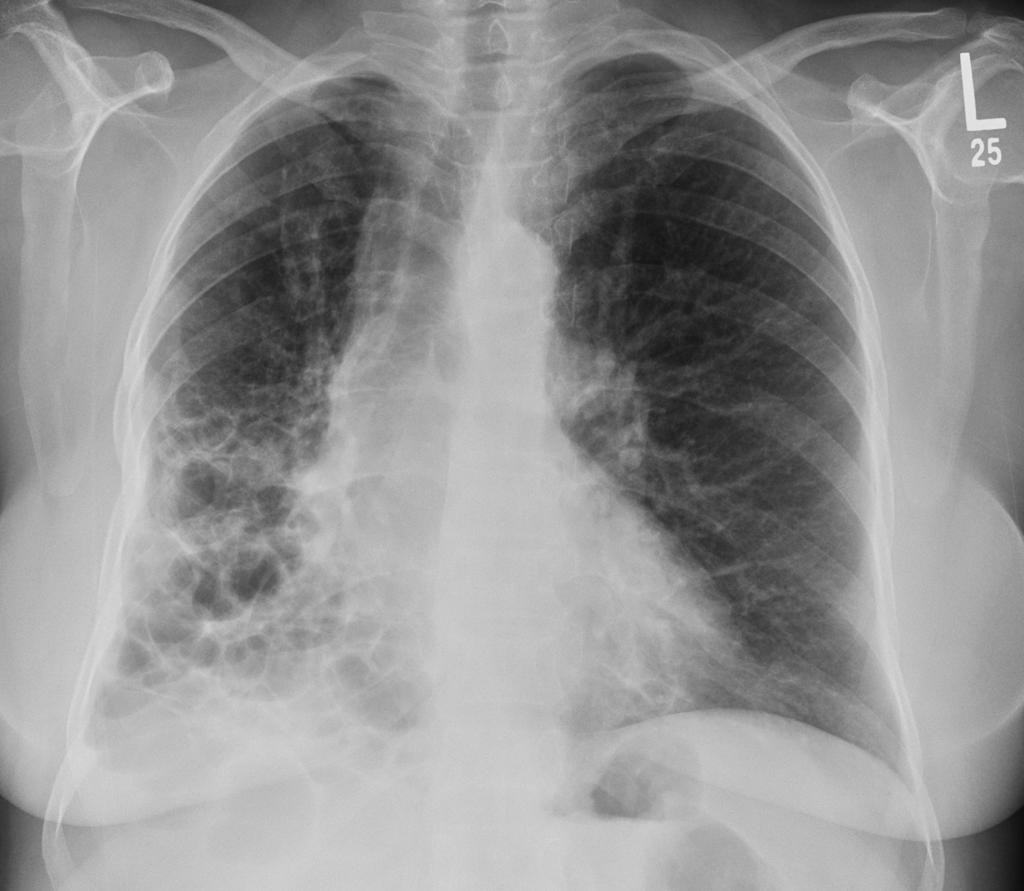

说到间质性肺疾病的发病机制,很多人可能会想到复杂的医学术语和看不懂的病理图片

其实,这个过程就像一场"肺部装修工程"出了大问题,原本井然有序的"施工现场"变得一团糟,最后整个"建筑结构"都被破坏了